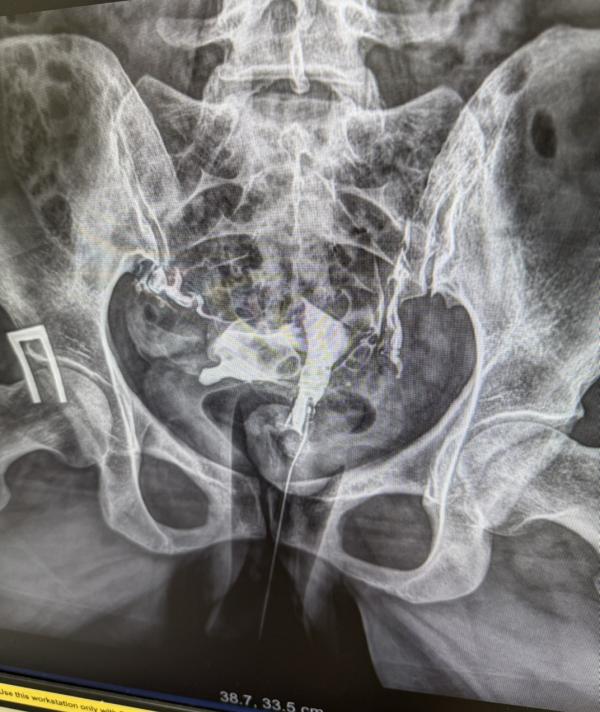

Сделала сегодня ГСГ маточных труб. Трубы проходимы, ни каких патологий нет. Три года назад на лапароскопии были с признаками хр.воспаления, где то расширены и извитые. Прикладываю рентген с контрастом. Может кто понимает, где там трубы? Я обвела красным по моему мнению трубы, синим матка 🤭